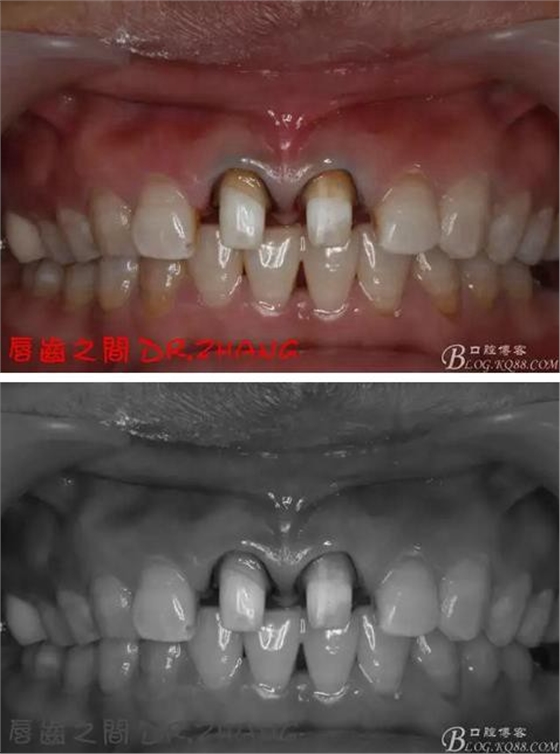

復(fù)診:腫脹明顯消失 患者自訴感覺良好 溝通后決定拆除11 21兩顆烤瓷冠后重新修復(fù) 去冠器直接去冠 去除11根管內(nèi)的充填物 15#K銼疏通根管 11 21根長均為16MM平斷面 薩尼S3系統(tǒng)機擴至2S 期間不斷用氯己定和鹽水交替沖洗 吸潮紙尖干燥根管后06 25#試尖

思博安熱牙膠系統(tǒng)根充 燙斷至根尖三分之一處后纖維樁恢復(fù)牙體組織

牙體預(yù)備后 硅橡膠取模 臨時牙恢復(fù)形態(tài)